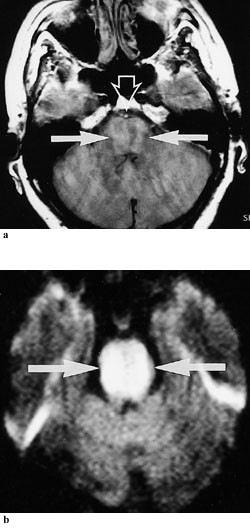

Cerebral CT halvannen time etter sykdomsdebut viste infarktforandringer i høyre parietalområde. Ultralydundersøkelse av a. basilaris viste lav blodstrømshastighet i proksimale avsnitt, forenlig med en distal obstruksjon. To og en halv time etter symptomdebut ble det gitt intravenøs trombolytisk behandling. Etter tre kvarter gikk den venstresidige hemiparalysen tilbake i løpet av minutter og hun ble nærmest symptomfri. I løpet av natten reokkluderte imidlertid a. basilaris og hun utviklet et komplett ”locked-in syndrome” (fig 1). Etter to dager var hun bevisstløs. Hun gjenvant ikke bevisstheten og døde ti dager etter sykdomsdebut.